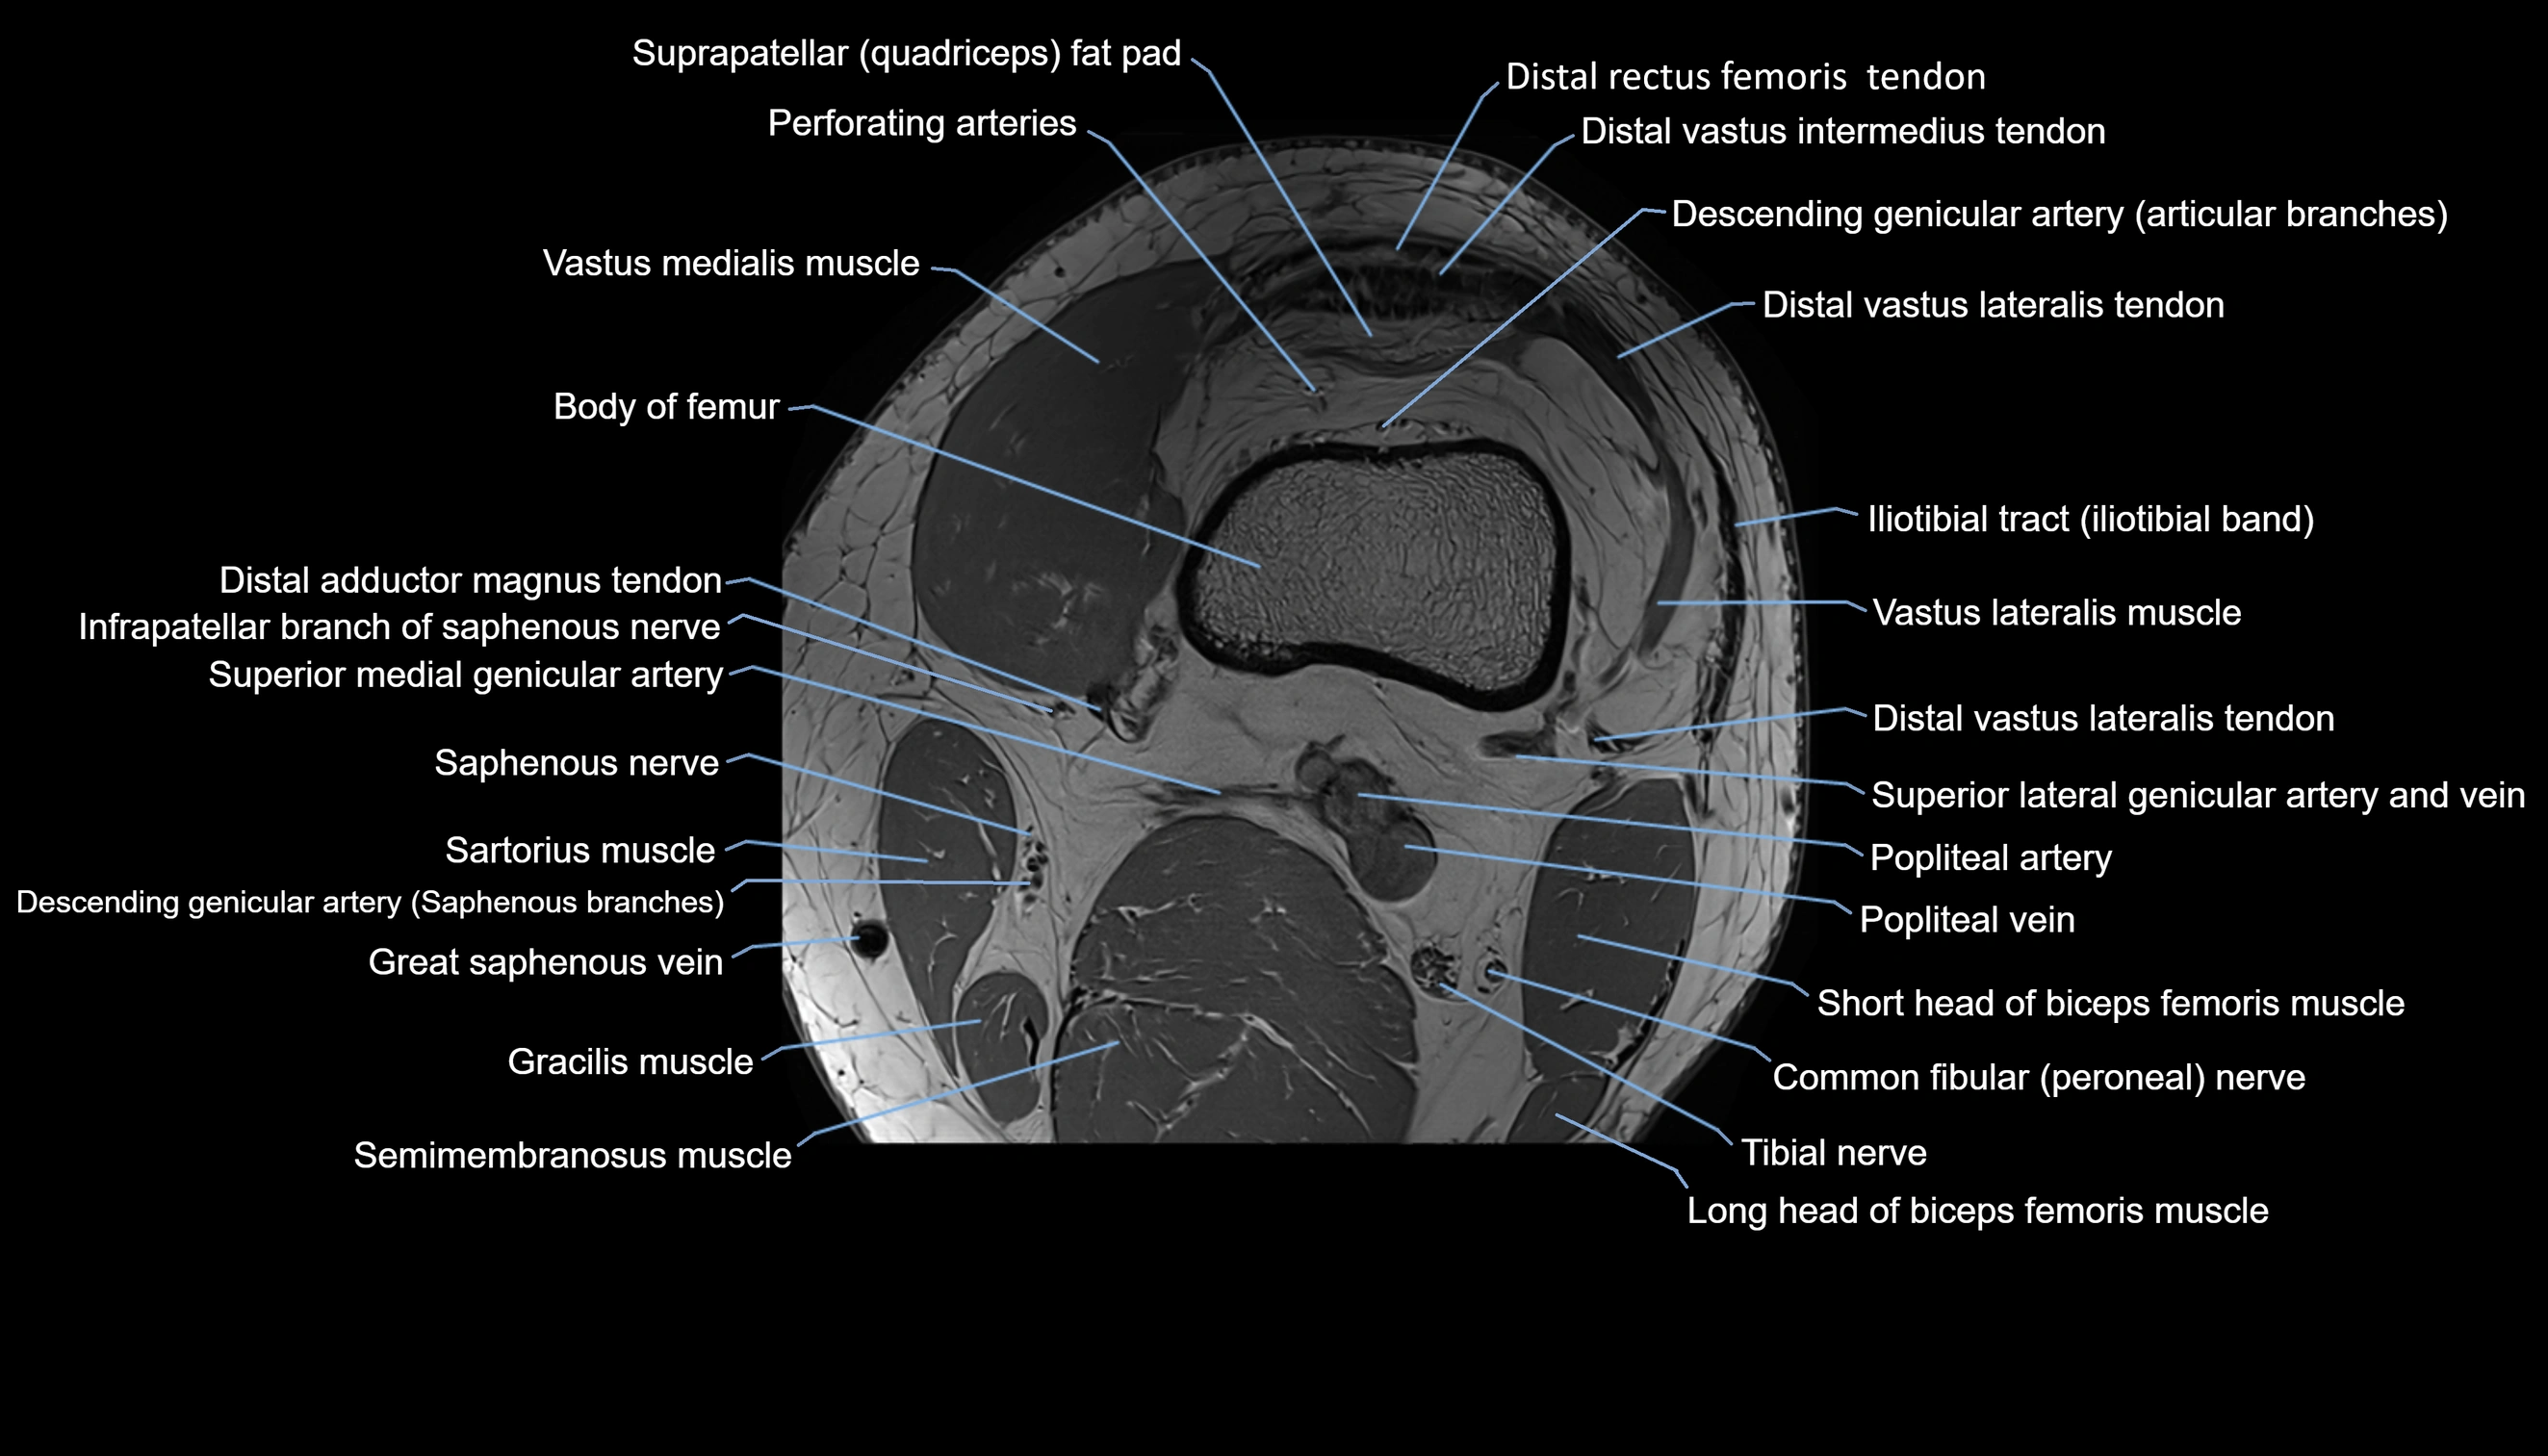

- Body of femur

- Distal rectus femoris tendon

- Distal vastus intermedius tendon

- Distal vastus lateralis tendon

- Vastus lateralis muscle

- Vastus medialis muscle

- Distal adductor magnus tendon

- Infrapatellar branch of saphenous nerve

- Superior medial genicular artery

- Sartorius muscle

- Descending genicular artery (Saphenous branch)

- great saphenous vein

- Gracilis tendon (Distal)

- Semimembranosus muscle

- Popliteal artery

- Popliteal vein

- Biceps femoris muscle (Short head)

- Common fibular nerve

- Tibial nerve

- Plantaris muscle

- Soleus muscle